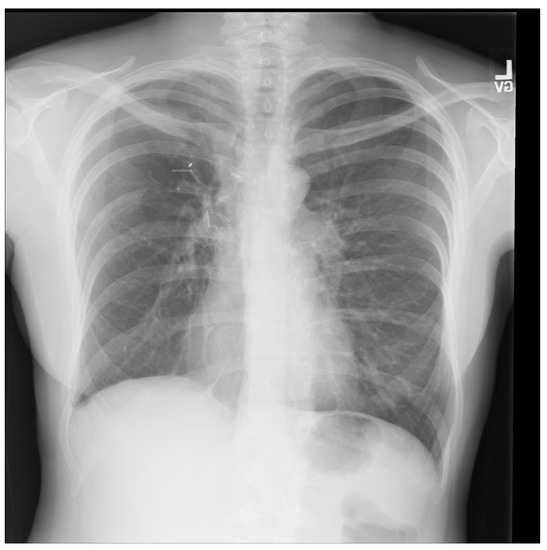

For a more intuitive understanding, we visualize a sample of each category in Figure 9, Figure 10 and Figure 11.

Figure 9. Covid sample: X-ray Image dataset.

Applsci 13 00454 g009